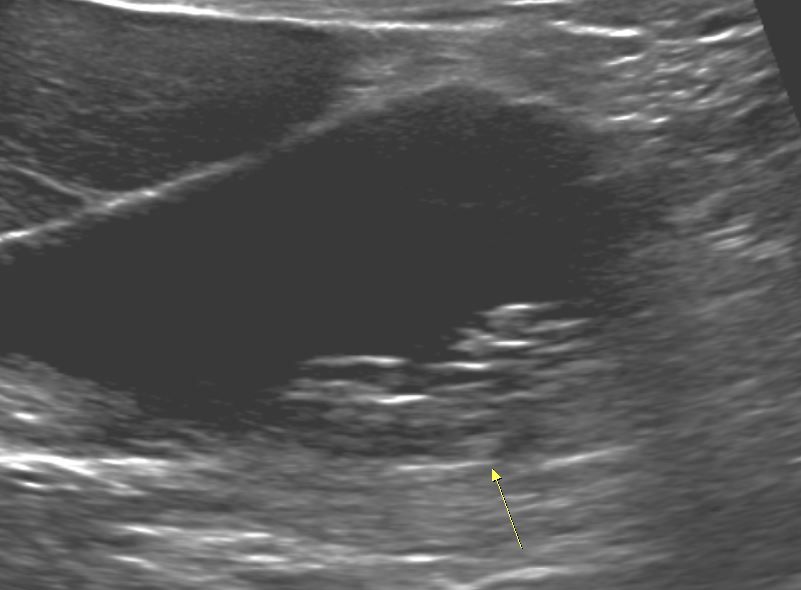

소노그래퍼 선생님은 자세에 따른 움직임과 신호를 근거로 슬러지(결석)이라고 의견 주신다는데 저는 영상에서 음영이 나타나지 않아 암은 아닐까 너무 걱정 됩니다.

간은 이상 없고 췌장 body duct 2.3mm check

GB Polyp 다수 발견되었고 가장 큰 건 9mm입니다.

초음파 사진을 두 장만 봐서는 판단이 어렵긴 합니다만, 체위 변경에 따른 움직임을 실시간으로 확인했다면 작은 돌이나 슬러지일 가능성이 높습니다.

다만 담석은 담낭 용종과 함께 발견된 경우 수술의 적응증이 되므로 수술이 가능한 병원에서 담낭절제술에 대한 상담도 함께 받으시는 것이 좋겠습니다.